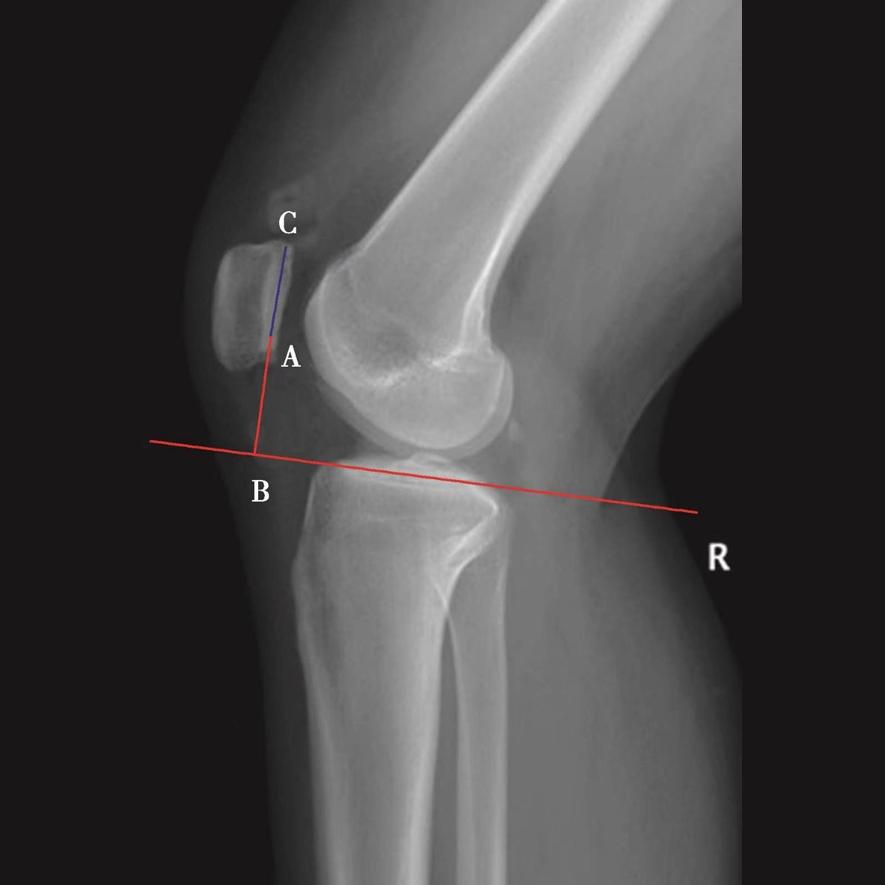

03、胫骨后倾角的评估

测量胫骨后倾角时先要观察胫骨上段及其与腓骨的位置关系,选择无明显胫骨旋转的,胫骨平台轮廓清晰的膝关节X侧位片。方法1测得的胫骨后倾角范围是11.74°±3.87°,方法2测得的胫骨后倾角范围是8.91°±3.57°,方法3测得的胫骨后倾角范围是6.21°±3.51°。

图15 胫骨后倾角的评估

用量角器测量胫骨内侧平台前后缘连线分别与胫骨中上段前侧骨皮质切线的垂线(图15A)、胫骨结节下胫骨中上段轴线的垂线(图15B)以及胫骨后侧皮质切线的垂线(图15C)的夹角,即胫骨后倾角(∠AOB)。